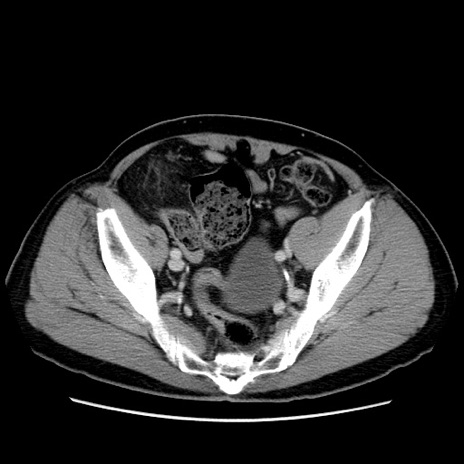

症例34(横断像)

【症例】60歳代 男性

【主訴】右鼠径部膨隆

【現病歴】1年程前より右鼠径部膨隆あり。自己にて還納可能だったため放置していた。3時間前より右鼠径部の脱出を認め、還納困難となり受診。

【既往歴】高血圧

【身体所見】右鼠径部に小児頭大の膨隆あり。弾性硬であり、用手還納は困難。左鼠径部にも膨隆を認める。脱出はなし。

【データ】WBC 15500、CRP 測定なし